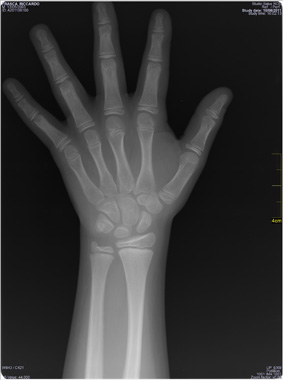

Il pene misurava 7,5 cm, 90� pc secondo Schonfeld1, stadio G3 di Tanner. Nella norma il resto dell'esame obiettivo generale. Pressione arteriosa 98-60 mm Hg (50� pc). Veniva richiesta l'Rx di mano e polso sinistro per valutazione dell'et� ossea (Figura 3).

Figura 3. Radiografia di mano e polso sinistro. Et� ossea di quasi 13 anni sec. Greulich e Pyle (+5 anni rispetto all'et� cronologica).